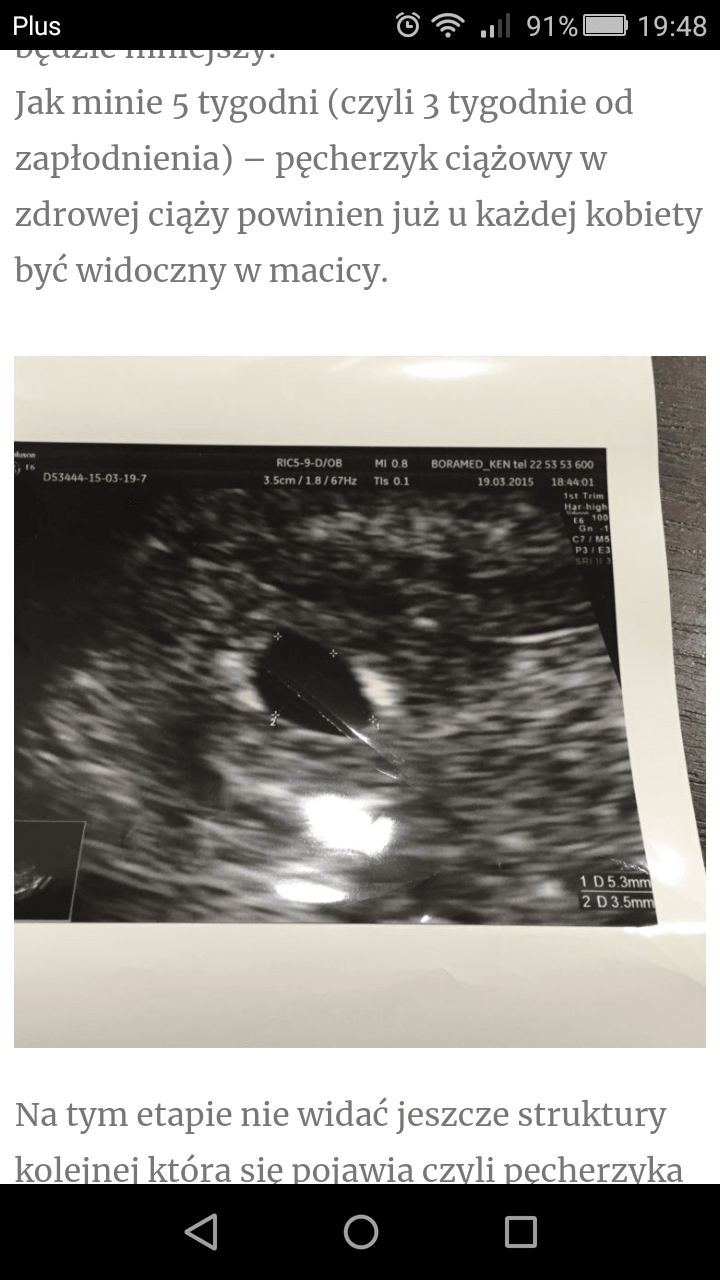

I właśnie u mnie jest już wlaśnie ten pęcherzyk zoltkowy. Czyli wszystko chyba jest w porządku.

Lekarka mówiła coś o 5 tyg i paru dniach, czyli by się zgadzało z tym wszystkim co tu piszą.